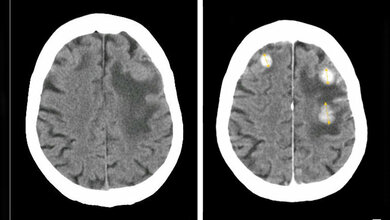

Ab einer bestimmten Größe werden einzelne Hirnmetastasen oft operativ mithilfe einer mikrochirurgischen Resektion entfernt. Bei der stereotaktischen Radiochirurgie (engl. stereotactic radiosurgery = SRS) hingegen werden sie zumeist einmalig, hochdosiert und zielgerichtet mithilfe von Kobalt-60-Gamma-Strahlungsquellen bestrahlt. Anders als bei der Ganzhirnbestrahlung (GHB) soll so nur das Tumorgewebe der hohen Strahlendosis ausgesetzt und das umliegende Gewebe geschont werden. Die Vor- und Nachteile einer solchen einzeitigen SRS-Behandlung im Vergleich zur Operation und zur GHB hat das Institut für Qualität und Wirtschaftlichkeit im Gesundheitswesen (IQWiG) nun in einer Nutzenbewertung untersucht.

Das Ergebnis fällt eindeutig aus. Im Vergleich zur vollständigen Bestrahlung des Gehirns (GHB) schone die SRS die Gedächtnisleistung der Patientinnen und Patienten. Zudem benötige die einzeitige SRS nur eine Behandlung und könne bei einem möglichen Fortschreiten der Erkrankung erneut eingesetzt werden. In der Gesamtschau der Studiendaten ergebe sich daraus ein Anhaltspunkt für einen höheren Nutzen der SRS, betont das IQWiG.

Für den Vergleich der SRS mit der GHB sei die Datenbasis deutlich besser, denn es liegen insgesamt sechs randomisierte kontrollierte Studien (RCT) vor: fünf mit mäßiger Ergebnissicherheit und eine Studie mit hoher Ergebnissicherheit. Darin zeige sich für die Gedächtnisleistung als Teilkomponente der kognitiven Funktion ein Anhaltspunkt für einen höheren Nutzen der SRS. Aufgrund der vorliegenden Daten sei eine Verkürzung der Überlebenszeit nicht ganz auszuschließen, aber nicht wahrscheinlich. Offen bleibe der Vergleich in Bezug auf andere Komponenten der kognitiven Funktion (z. B. den Sprachfluss) sowie auf die Aktivitäten des täglichen Lebens, die Nebenwirkungen der Therapie und die gesundheitsbezogene Lebensqualität. Prinzipiell biete die einzeitige SRS im Vergleich zur GHB die therapieimmanenten Vorteile, dass sie bei einer einzigen Behandlung (statt zehn bis zwanzig) mit sehr viel weniger Aufwand für die Betroffenen verbunden sei und sich zudem wiederholen lasse, beispielsweise bei Rezidiven, erläutert das IQWiG.